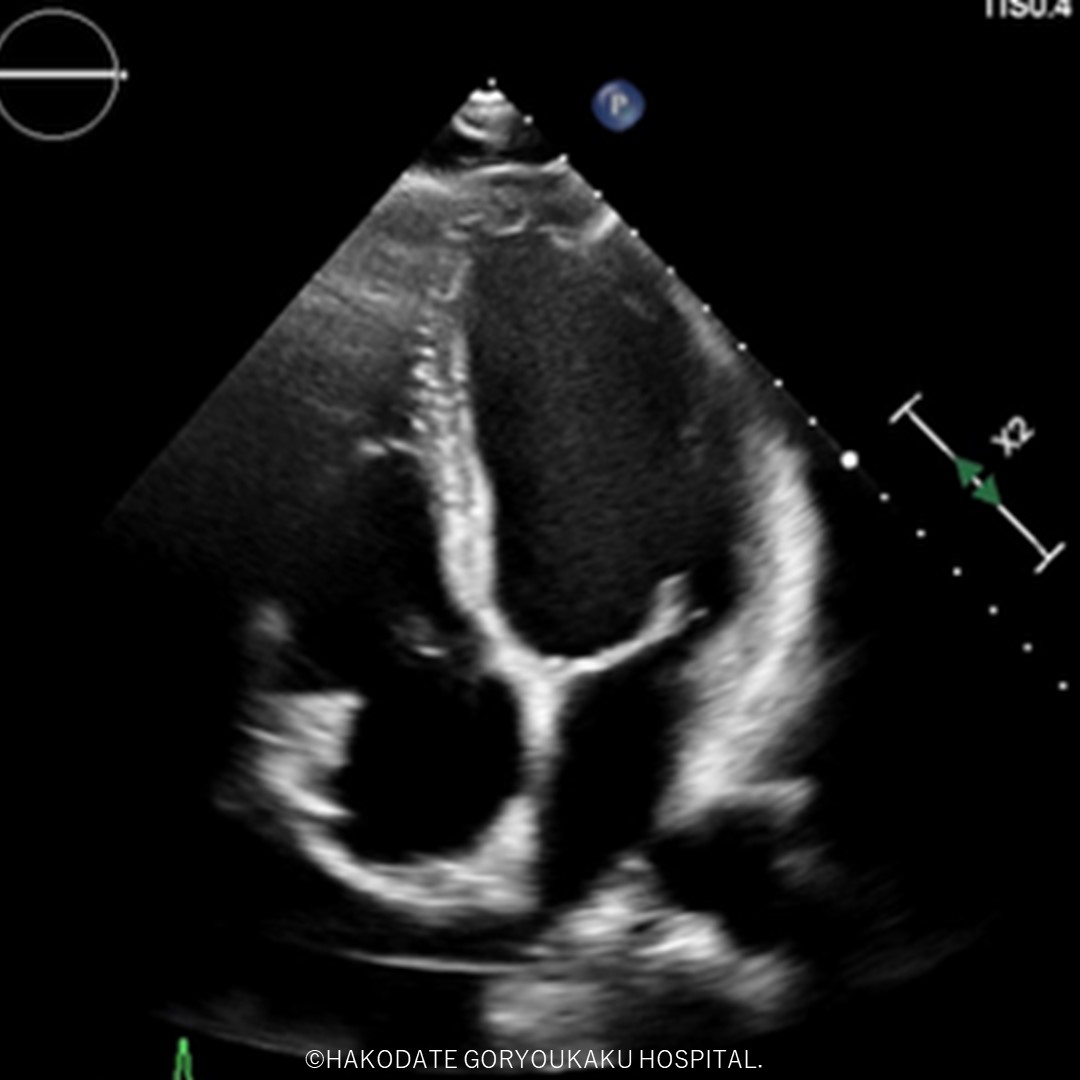

心エコー検査は、超音波ビームを用いて心臓をリアルタイムに画像・映像化し、心臓の動きやカタチ、血流の方向などを観察する検査です。